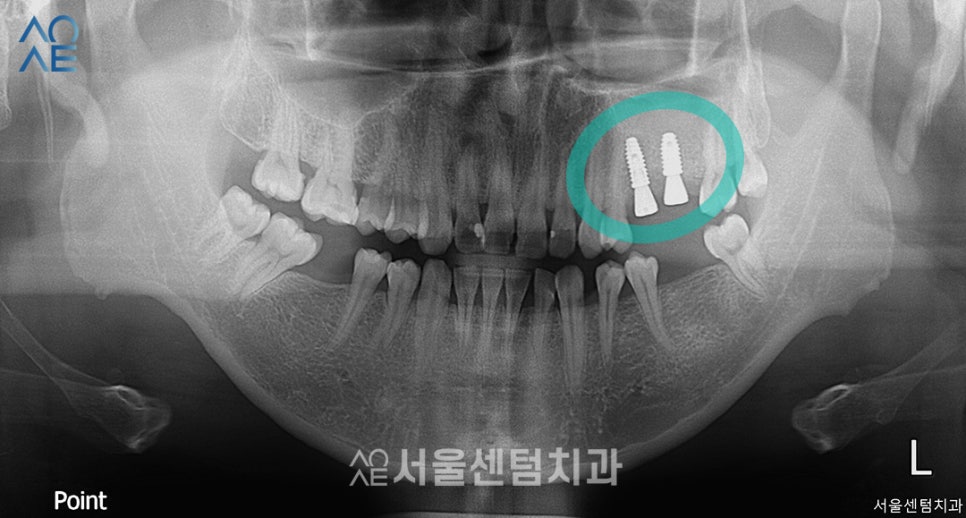

왼쪽 위 작은어금니, 큰어금니 위치에

임플란트를 식립을 계획하였으나

식립공간이 부족한 케이스였습니다.

따라서 상악동수술 동반한 임플란트 식립과

뼈이식을 진행하게 되었습니다.

- 26

잇몸뼈가 충분히 만들어질 시간을 두고

약 3개월 후에 다시 내원하셨습니다.

다행히 잘 형성되고 있어서

보철물 제작도 진행하기로 했습니다.

엑스레이 사진을 보시면

픽스처가 골융합이 잘 되어서

안정적으로 잘 식립된 것을 확인할 수 있습니다.

여기서는 2차수술이 필요 없는

일체형을 식립하여 바로 보철물 제작을 하였습니다.